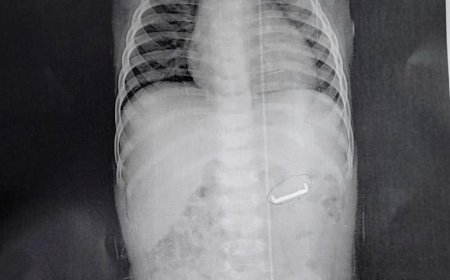

فى إطار جهود أجهزة وزارة الداخلية لكشف ملابسات بإجراء التحريات وجمع المعلومات وذلك بتوجيهات م السيد مساعد الوزير ..مدير أمن القارة اللواء “ طارق راشد محفوظ ” ، و السيد مساعد الوزير “اللواء علاء بشندى ” مدير الإدارة العامة لمباحث الاهرة، ما تبلغ لقسم شرطة البساتين بديرية أمن القاهر من إحدى المستشفيات بإستقبالها (طاب - مقيم بمحافظة الجيزة).. مصاب بطعن نافذة بالبطن والصدر وإشتباه نزيف البطن.

بالإنتقال وسؤاله قرر بأنه حل تواجده أمام الجامعة محل دراسته بائرة القسم حدثت مشادة كلامية بينه بين أحد الباعة الجائلين إثر إرتطامه به ، قام على أثرا بائع آخر بالتدخل والتعدى عليه باضرب بإستخدام سلا أبيض كان بحوزته.. نتج عن ذلك إصابته المنوه عنها.